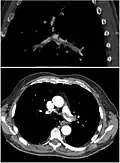

CT pulmonary angiography

CT pulmonary angiography (CTPA) is a pulmonary angiogram obtained using computed tomography (CT) with radiocontrast rather than right heart catheterization. Its advantages are that it is accurate, it is non-invasive, it is more often available, and it may identify other lung disorders in case there is no pulmonary embolism. The accuracy and non-invasive nature of CTPA also make it advantageous for people who are pregnant.[61]

- On CT scan, pulmonary emboli can be classified according to the level along the arterial tree.

- Segmental and subsegmental pulmonary emboli on both sides

- CT pulmonary angiography showing a "saddle embolus" at the bifurcation of the main pulmonary artery and thrombus burden in the lobar arteries on both sides

- Pulmonary embolism (white arrow) that has been long-standing and has caused a lung infarction (black arrow) seen as a reverse halo sign

Assessing the accuracy of CT pulmonary angiography is hindered by the rapid changes in the number of rows of detectors available in multidetector CT (MDCT) machines.[62] According to a cohort study, single-slice spiral CT may help diagnose detection among people with suspected pulmonary embolism.[63] In this study, the sensitivity was 69% and specificity was 84%. In this study which had a prevalence of detection was 32%, the positive predictive value of 67.0% and negative predictive value of 85.2%. However, this study's results may be biased due to possible incorporation bias, since the CT scan was the final diagnostic tool in people with pulmonary embolism. The authors noted that a negative single-slice CT scan is insufficient to rule out pulmonary embolism on its own. A separate study with a mixture of 4-slice and 16-slice scanners reported a sensitivity of 83% and a specificity of 96%, which means that it is a good test for ruling out a pulmonary embolism if it is not seen on imaging and that it is very good at confirming a pulmonary embolism is present if it is seen. This study noted that additional testing is necessary when the clinical probability is inconsistent with the imaging results.[64] CTPA is non-inferior to VQ scanning, and identifies more emboli (without necessarily improving the outcome) compared to VQ scanning.[65]